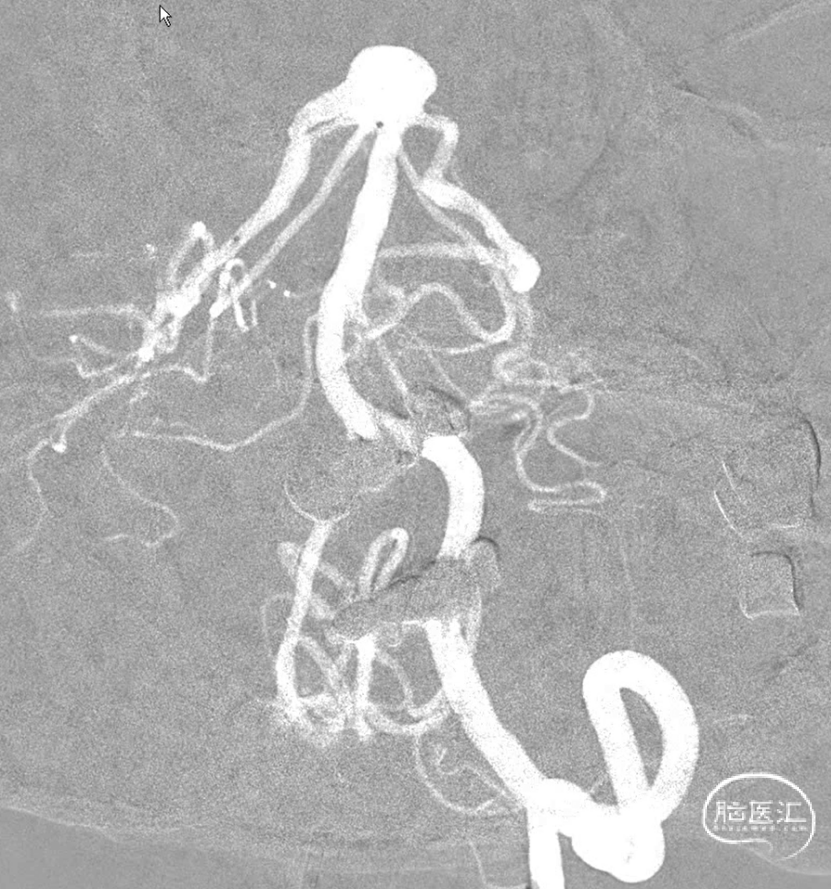

支架释放完毕,感觉还是不太死心,于是调整了微导管几次,由于弹簧圈和支架的阻挡,还是调不进去,如果继续尝试,可能有增加支架内形成血栓的概率和导管可能戳破动脉瘤的风险。于是绝定再造个影看看。

这个角度,感觉残留一些。

换了个角度,感觉还可以。

标准侧位发现,这个位置有些残留,角度还是比较刁的,不太好到位。虽然有这么一点小遗憾。但是从患者是未破裂动脉瘤,及减少患者风险为第一位的角度上看,还是可以考虑一下。因此毅然决定收手。术后患者安好。

静下来想想,有的时候我们追求完美,让手术和患者得到最大的受益无可厚非。但是有的时候能及时收手,减少患者由于增加操作而带来的风险,未尝不是一种正确的选择。仅为个人观点,与诸君分享。同时感谢各位关注。